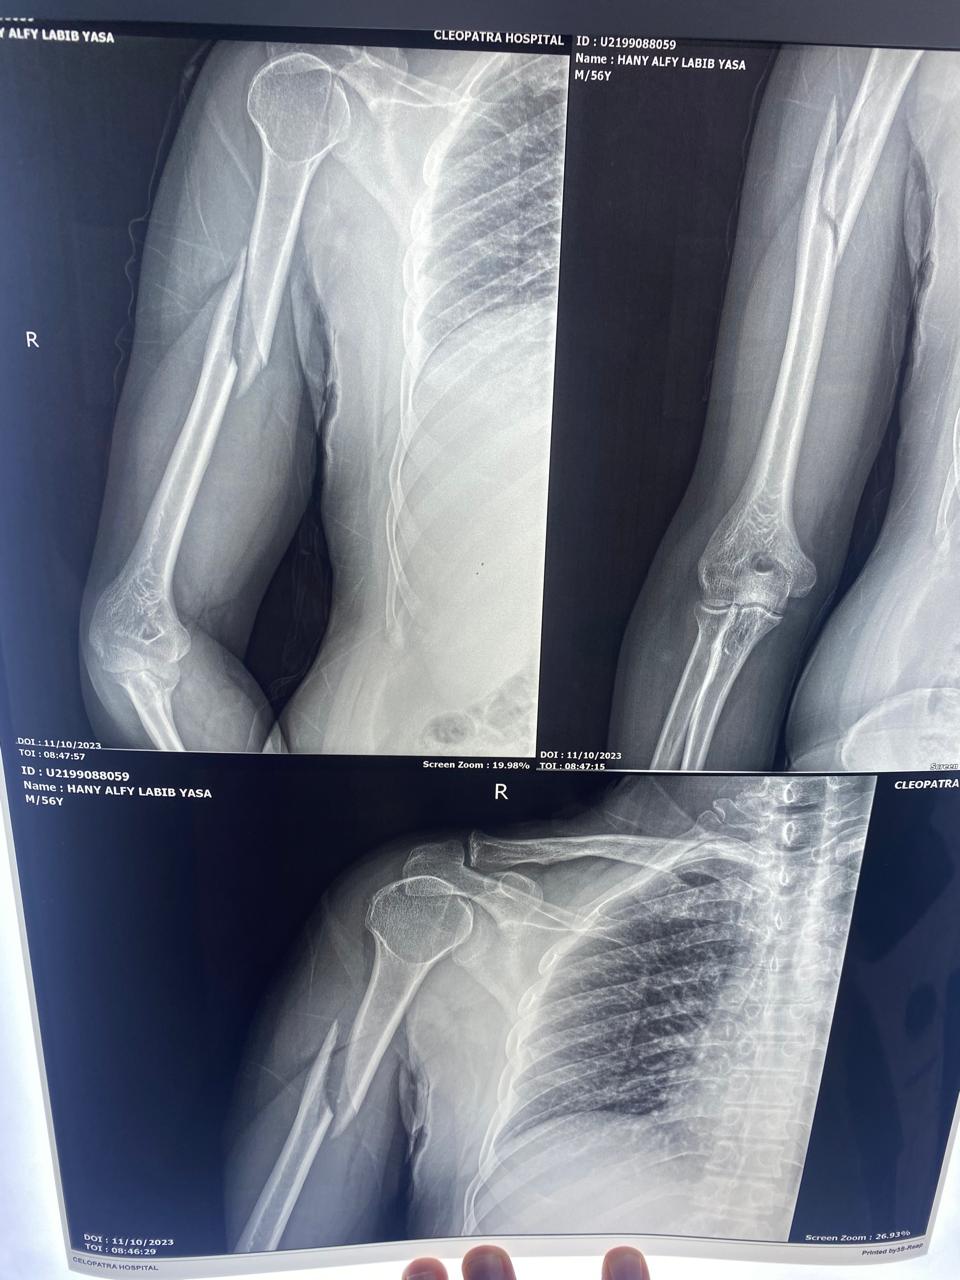

الاشعات بعد التثبيت تبين رجوع الكسر لطبيعته تمامًا.